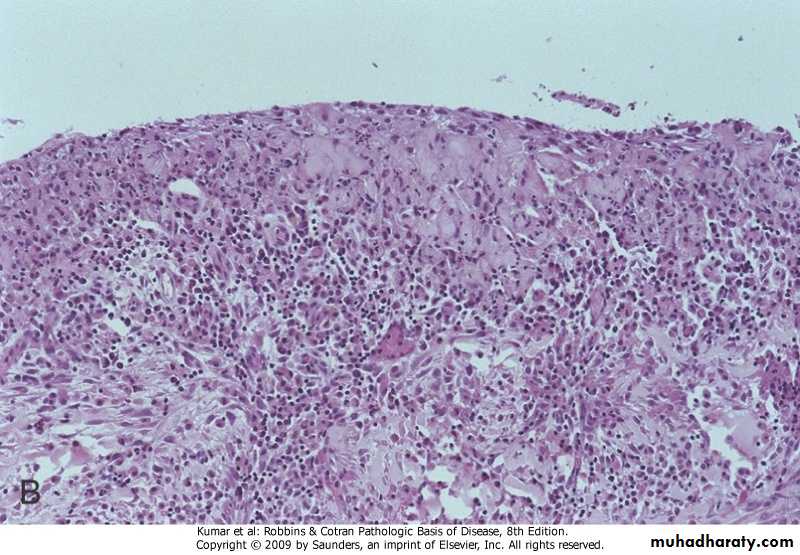

B

CHRONIC CHOLECYSTITIS : Grey white thikening of the blader wall with ulceration of the mucosa

Chronic cholecystitis